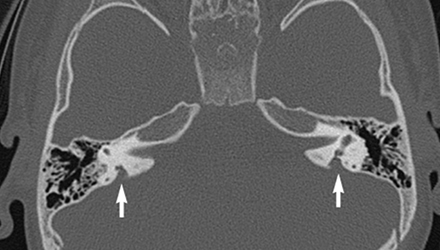

SLC26A4基因定位于人類染色體7q31,SLC26A4基因和大前庭導(dǎo)水管綜合征相關(guān)突變位點(diǎn)的發(fā)現(xiàn),證實(shí)SLC26A4是大前庭導(dǎo)水管綜合征的責(zé)任基因。

我們平時(shí)提到的“一巴掌打聾”、“一跤摔聾”其實(shí)都與SLC26A4基因突變有關(guān),絕大多數(shù)大前庭導(dǎo)水管綜合征都是SLC26A4基因突變?nèi)堑牡湣?/p>

SLC26A4基因編碼一種叫“Pendrin”的跨膜轉(zhuǎn)運(yùn)蛋白,在機(jī)體離子成分平衡的維持中發(fā)揮重要作用。

在內(nèi)耳,Pendrin表達(dá)于內(nèi)淋巴管、內(nèi)淋巴囊、橢圓囊、球囊等處,異變的蛋白將對這些結(jié)構(gòu)的正常生理功能產(chǎn)生影響,引發(fā)聽損。

SLC26A4基因突變導(dǎo)致的大前庭導(dǎo)水管綜合征的典型表現(xiàn)為兒童時(shí)期的聽力損失,90%的患者為雙側(cè)性,聽力損失程度不一,可表現(xiàn)為接近正常或重-極重度。

病程可為穩(wěn)定性、進(jìn)行性或波動(dòng)性,聽力可逐步下降至全聾;跌倒、撞擊等行為或無外界影響都可能引發(fā)聽力的下降。